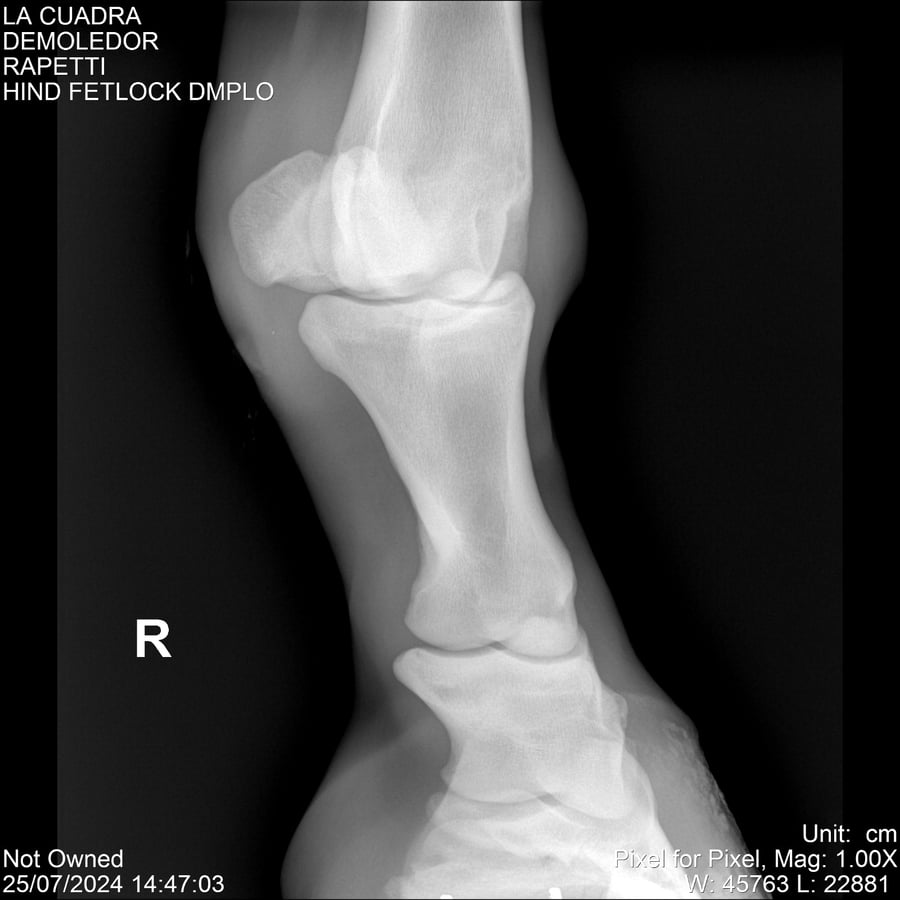

LOTE 14, DEMOLEDOR 🔥 🔥 🔥 Lote Anterior Volver al remate Lote Siguiente Ficha Contacto Montevideo - Ficha del Lote Identificador: #284454 Categoría: Yeguarizos Montevideo - 89 Visualizaciones ClicData Contacto Empresa: Abelenda N. R., Walter Hugo Nombre*: Teléfono* : E-mail* : Mensaje Enviar Registrese gratis Este contenido Exclusivo está disponible sólo para usuarios registrados Ingresar